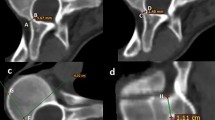

Each CT scan was opened using AMIRA with synchronized axial, coronal, and sagittal displays. The image contrast levels were standardized to enable clear soft tissue and bone demarcation at the vertebral pedicles. The relevant vertebral body was identified by counting upward from the sacrum and confirmed by counting the rib levels superiorly and inferiorly. For the pedicle to be measured, the local axial viewing plane (Fig. 1) was adjusted to be parallel to the superior and inferior endplates of the vertebrae in question (Red line in Fig. 1C) and aligned with the pedicle axis (Red line in Fig. 1B). When the superior and inferior endplate planes were not parallel owing to vertebral wedging, an orientation approximately halfway between (ie, bisecting) the two endplate inclinations was selected. The local sagittal viewing plane (Fig. 1B) then was adjusted such that it was in line with the pedicle axis and perpendicular to the local axial plane (Green line in Fig. 1A). The right pedicle was identified in a similar manner and the local viewing plane orientation again adjusted to be in line with the right pedicle axis in the axial and sagittal viewing planes.

The local (A) axial viewing plane with a sagittal slice (green line) in line with the pedicle axis, (B) sagittal viewing plane with an axial slice (red line) in line with the pedicle axis, and (C) coronal viewing plane with an axial slice (red line) approximately parallel to the superior and inferior endplates are shown.

Anatomic landmarks were identified and measured on each pedicle (Fig. 2). The 3-D coordinates of 17 points (points A through Q) were identified on each pedicle (34 in total for each vertebra), with the appropriate distances and angles between these points (pedicle width, inner cortical pedicle width, pedicle length, chord length, transverse pedicle angle, pedicle height, inner cortical pedicle height, sagittal pedicle angle) calculated from the landmark locations (Fig. 2). These measurement definitions are similar to those described in the literature [7, 16, 18, 31], however we have taken measurements with the coronal, sagittal, and axial planes oriented to better represent the anatomic axes of the pedicle.

(A) This CT scan of a thoracic vertebrae in the local axial plane shows the outer cortical pedicle width (AC) and the inner cortical pedicle width (BD), where A is the lateral outer cortex margin, B is the lateral inner cortex margin, C is the medial outer cortex margin, and D is the medial inner cortex margin. (B) This scan of a thoracic vertebrae in the local axial plane shows chord length (EF), pedicle length (FG), and transverse pedicle angle (angle between EG and HI), where E is the anterior edge of the vertebral body along the pedicle axis, F is the posterior edge of the vertebra along the pedicle axis, G is a point in line with the posterior longitudinal ligament along the pedicle axis, H is the sagittal midvertebral line at the anterior aspect of the vertebral body, and I is the sagittal midvertebral line at the meeting of the laminae. (C) This CT scan of a thoracic vertebrae in the local sagittal plane shows the pedicle height (JL) and inner cortical pedicle height (KM), where J is the superior outer cortex margin, K is the superior inner cortex margin, L is the inferior outer cortex margin, and M is the inferior inner cortex margin. (D) This scan of a thoracic vertebrae in the local sagittal plane shows the sagittal pedicle angle (angle between the line NO and PQ), where NO is a line between the anterior (N) and posterior (O) aspects of the vertebrae angled midway between the superior and inferior endplates angles, while PQ is a line between the anterior (P) and posterior (Q) edges of the vertebrae along the pedicle axis in the sagittal viewing plane.